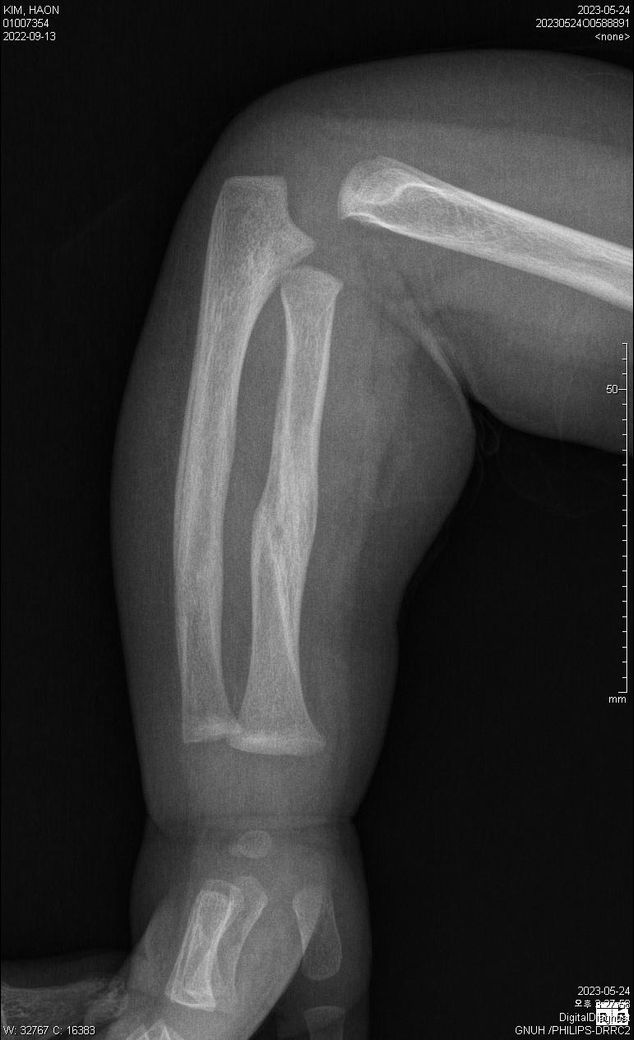

23.5.24 X-ray입니다.

양팔이 골절이 되었었는데요,

가골형성 시기인지,

재형성(리모델링) 시기인지 궁금합니다.

• 1번 째 사진

사진상으로 골유합이 잘 진행중입니다. 리모델링은 추후 수개월에서 수년까지 걸쳐서 일어나서 특정할순 없습니다.